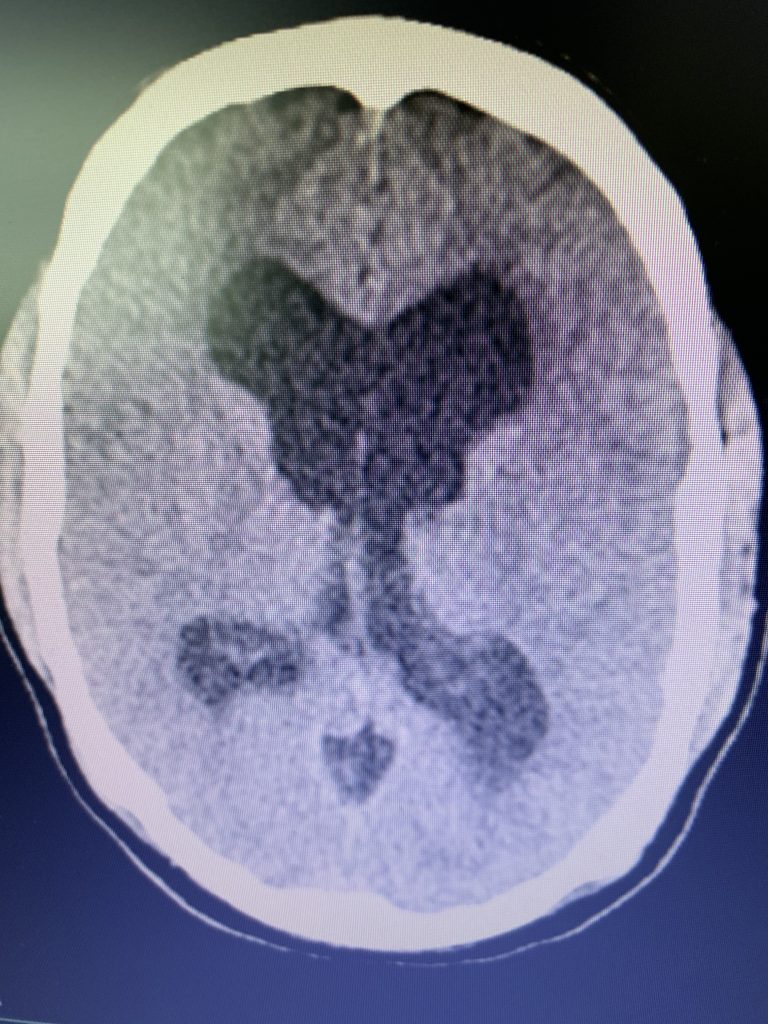

On initial examination, the patient was neurologically intact without complaints of headache. His imaging; however, did show hydrocephalus, most notably the lateral and third ventricles with a normal sized fourth ventricle. Given that the patient had no complaints, a decision was made to follow this expectantly and he was referred for a neuro-ophthalmologic evaluation, which confirmed no evidence of papilledema. MRI was otherwise negative.

Figure 1B,C: Pre-operative CT images.

Prior to shunting, a head CT was obtained and the head CT in addition to documenting a patten of obstructive hydrocephalus suggested a possible mass lesion compressing the aqueduct at its inferior aspect. Figure #1 demonstrates the hydrocephalus and the possible lesion. A decision was made at this point that the patient had obstructive hydrocephalus that was now symptomatic and he was taken for a laparoscopic-assisted ventriculoperitoneal shunt.